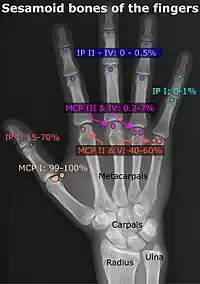

- Location and structure: Erica Chu, Donald Resnick, « MRI Web Clinic — June 2014: Sesamoid Bones: Normal and Abnormal » (consulté le )

- Prevalences: Chen W, Cheng J, Sun R et Zhang Z, « Prevalence and variation of sesamoid bones in the hand: a multi-center radiographic study. », Int J Clin Exp Med, vol. 8, no 7, , p. 11721–6 (PMID 26380010, PMCID 4565393) - « Poster Abstracts », Association for Sports Medicine of Serbia (Udruženje za medicinu sporta Srbije), (consulté le ), citing: Natsis K., Beletsiotis A., Terzidis I. et Gigis P., « A study of the accessory bones of the foot. Incidence in the Greek population-clinical significance »